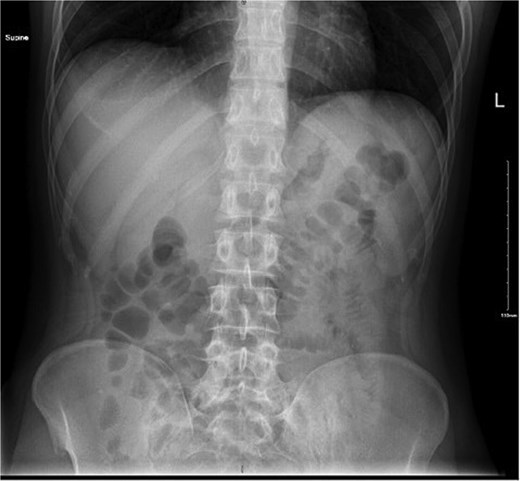

A computed tomography (CT) scan of the abdomen and pelvis revealed a linear hyperdense structure measuring 3.7 cm in length appearing inside the terminal ileum exiting the lumen medially towards the small bowel loops with no signs of free air, likely representing an ingested bone. There was an edematous wall thickening of the cecum and mucosal hyperenhancement of the appendix, which was likely reactive (Fig. 2).

CT scan showing linear hyperdense structure (arrow) within the terminal ileum perforating medially.